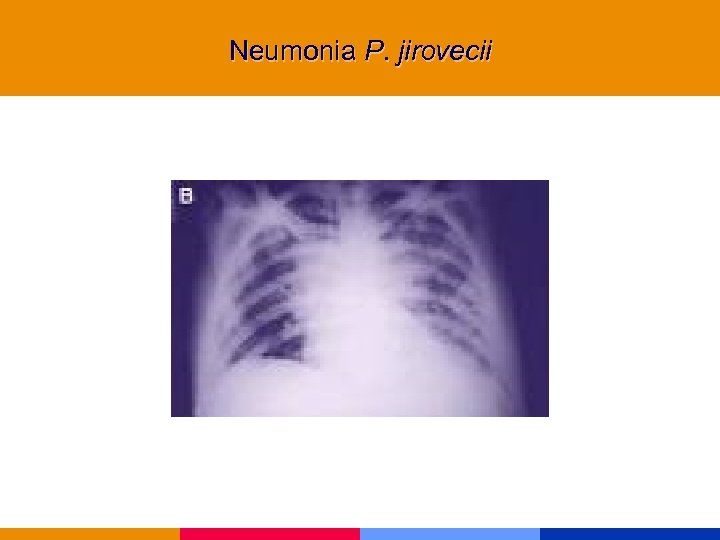

Neumonía por Pneumocistis jirovecii

Neumonía por Pneumocistis jirovecii

Neumonía por Pneumocistis jirovecii § CD 4 < 200 mm 3 § Comienzo insidioso: fiebre, tos seca, disnea. Hallazgos al examen físico incaracterísticos. § Lab: VSG: 50 mm. LDH, valor diagnóstico y pronóstico. Hipoxemia. § Rx infiltrado intersticial difuso, neumatocele, neumotórax. § TC de alta resolución.

Neumonía por Pneumocistis jirovecii § CD 4 < 200 mm 3 § Comienzo insidioso: fiebre, tos seca, disnea. Hallazgos al examen físico incaracterísticos. § Lab: VSG: 50 mm. LDH, valor diagnóstico y pronóstico. Hipoxemia. § Rx infiltrado intersticial difuso, neumatocele, neumotórax. § TC de alta resolución.

Neumonia P. jirovecii

Neumonia P. jirovecii

Neumonia P. jirovecii

Neumonia P. jirovecii

Neumonia P. jirovecii

Neumonia P. jirovecii

Neumonia P. jirovecii

Neumonia P. jirovecii

Neumonia P. jirovecii

Neumonia P. jirovecii

Neumonia P. jirovecii

Neumonia P. jirovecii

Neumonia P. jirovecii

Neumonia P. jirovecii